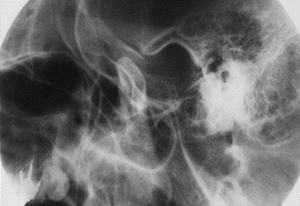

上の、レントゲン写真を御覧になって下さい。

これは、左の顎関節部のシューラー法という、レントゲン写真です。この方法では、顎関節部を非常に良く観察することが出来ます。

上の写真は閉口時(口を閉じた状態)です。